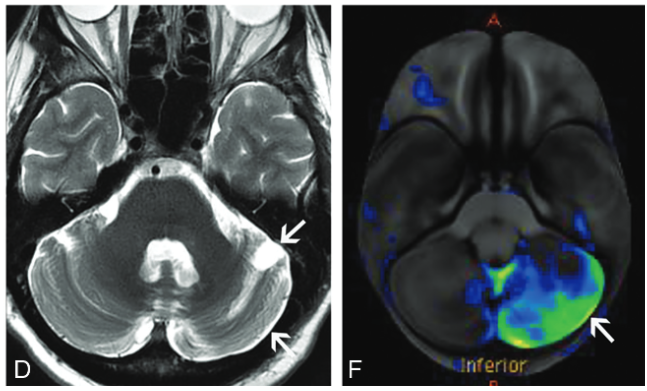

脳:脳幹脳炎

画像所見は,病期によって画像所見が異なる.

急性期は小脳や小脳脚,脳幹部のT2高信号and/or造影効果を呈する.

進行すると(慢性期),小脳や脳幹部が萎縮することがある.Waller変性を生じると橋の十字型T2高信号や中小脳脚のT2高信号を生じ,多系統萎縮症(MSA)と非常に類似した画像となりうる.

オリーブ核の異常肥大性変性(Hypertrophic olivary degeneration)が見られることがあり,歯状核ルイ体オリーブ経路が障害されるためと考えられる.